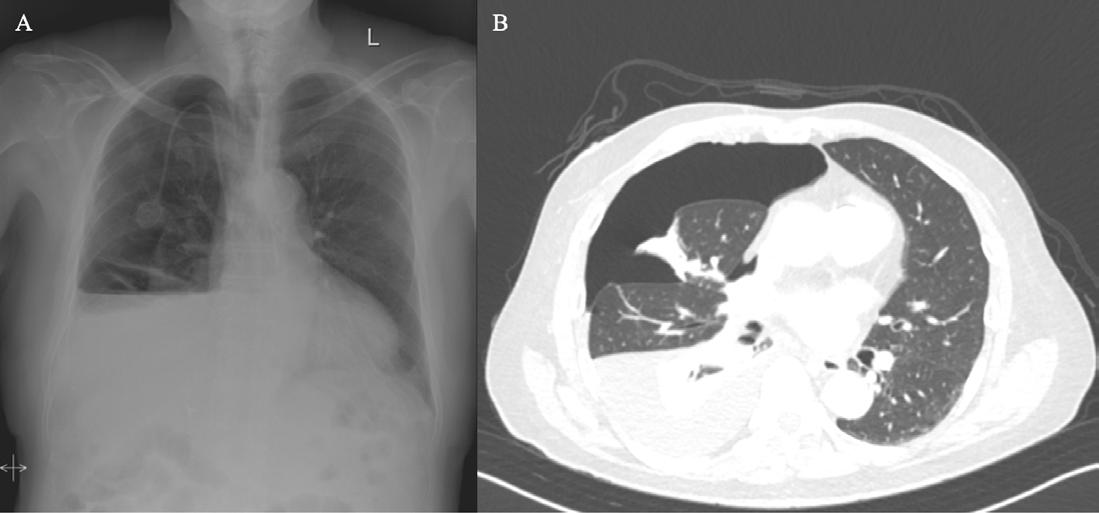

Editorial Leads

116 Immune Checkpoint Inhibitor-Associated Hydropneumothorax: A Rare Case Report with Histopathologic Insights

Fernandez J et al.